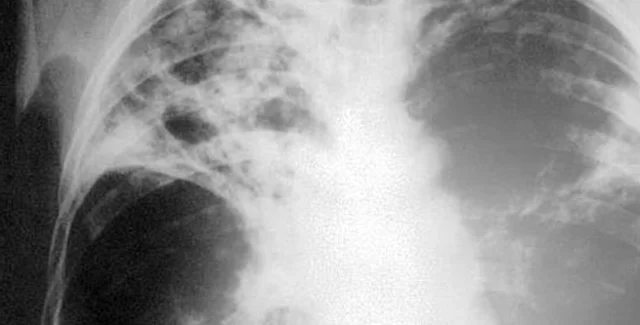

Туберкулез ежедневно убивает 4,5 тыс. человек

Несмотря на то, что с 1995 года 40 млн. человек вылечились от туберкулеза, каждый день эта болезнь продолжает уносить более 4,5 тысяч жизней. Об этом говорится в новом докладе Всемирной организации здравоохранения

Каждый год от палочки Коха гибнет около двух миллионов человек, уточняет директор отдела ВОЗ по борьбе с туберкулезом Марио Равильони.

"В прошлом году, несмотря на позитивные результаты, от туберкулеза погибли 1,7 млн. человек. В их числе 400 тыс. женщин, многие из которых были молодыми матерями. Это омрачает все наши успехи. Ни одно правительство не предпринимает достаточных усилий для обуздания этой болезни. Нам предстоит еще многое сделать", - заявил он.

Как сообщает радио ООН, Всемирная организация здравоохранения называет туберкулез всемирной пандемией. В 2009 году было зарегистрировано почти 9,5 млн. новых случаев заражения туберкулезом, среди них 3 млн. женщин и более миллиона ВИЧ-инфицированных.

В целом по миру бациллами туберкулеза инфицировано более двух миллиардов человек. Каждый десятый из них заболеет активной формой туберкулеза. Без лечения каждый такой больной может инфицировать в среднем 10-15 человек в год.

Кроме того, в мире растет число случаев туберкулеза с множественной лекарственной устойчивостью, не поддающейся стандартному лечению. В 2008 году этой формой туберкулеза заболели 440 тысяч человек. Более 50% всех таких случаев в мире пришлось на три страны — Индию, Китай и Россию.